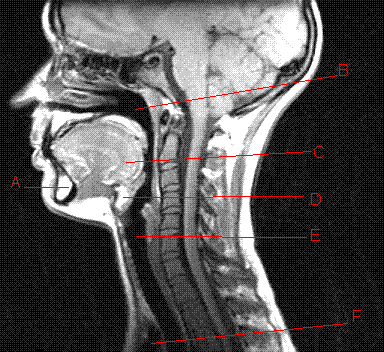

Where is the larynx located on this diagram (which letter)?

Letter E represents the layrnx